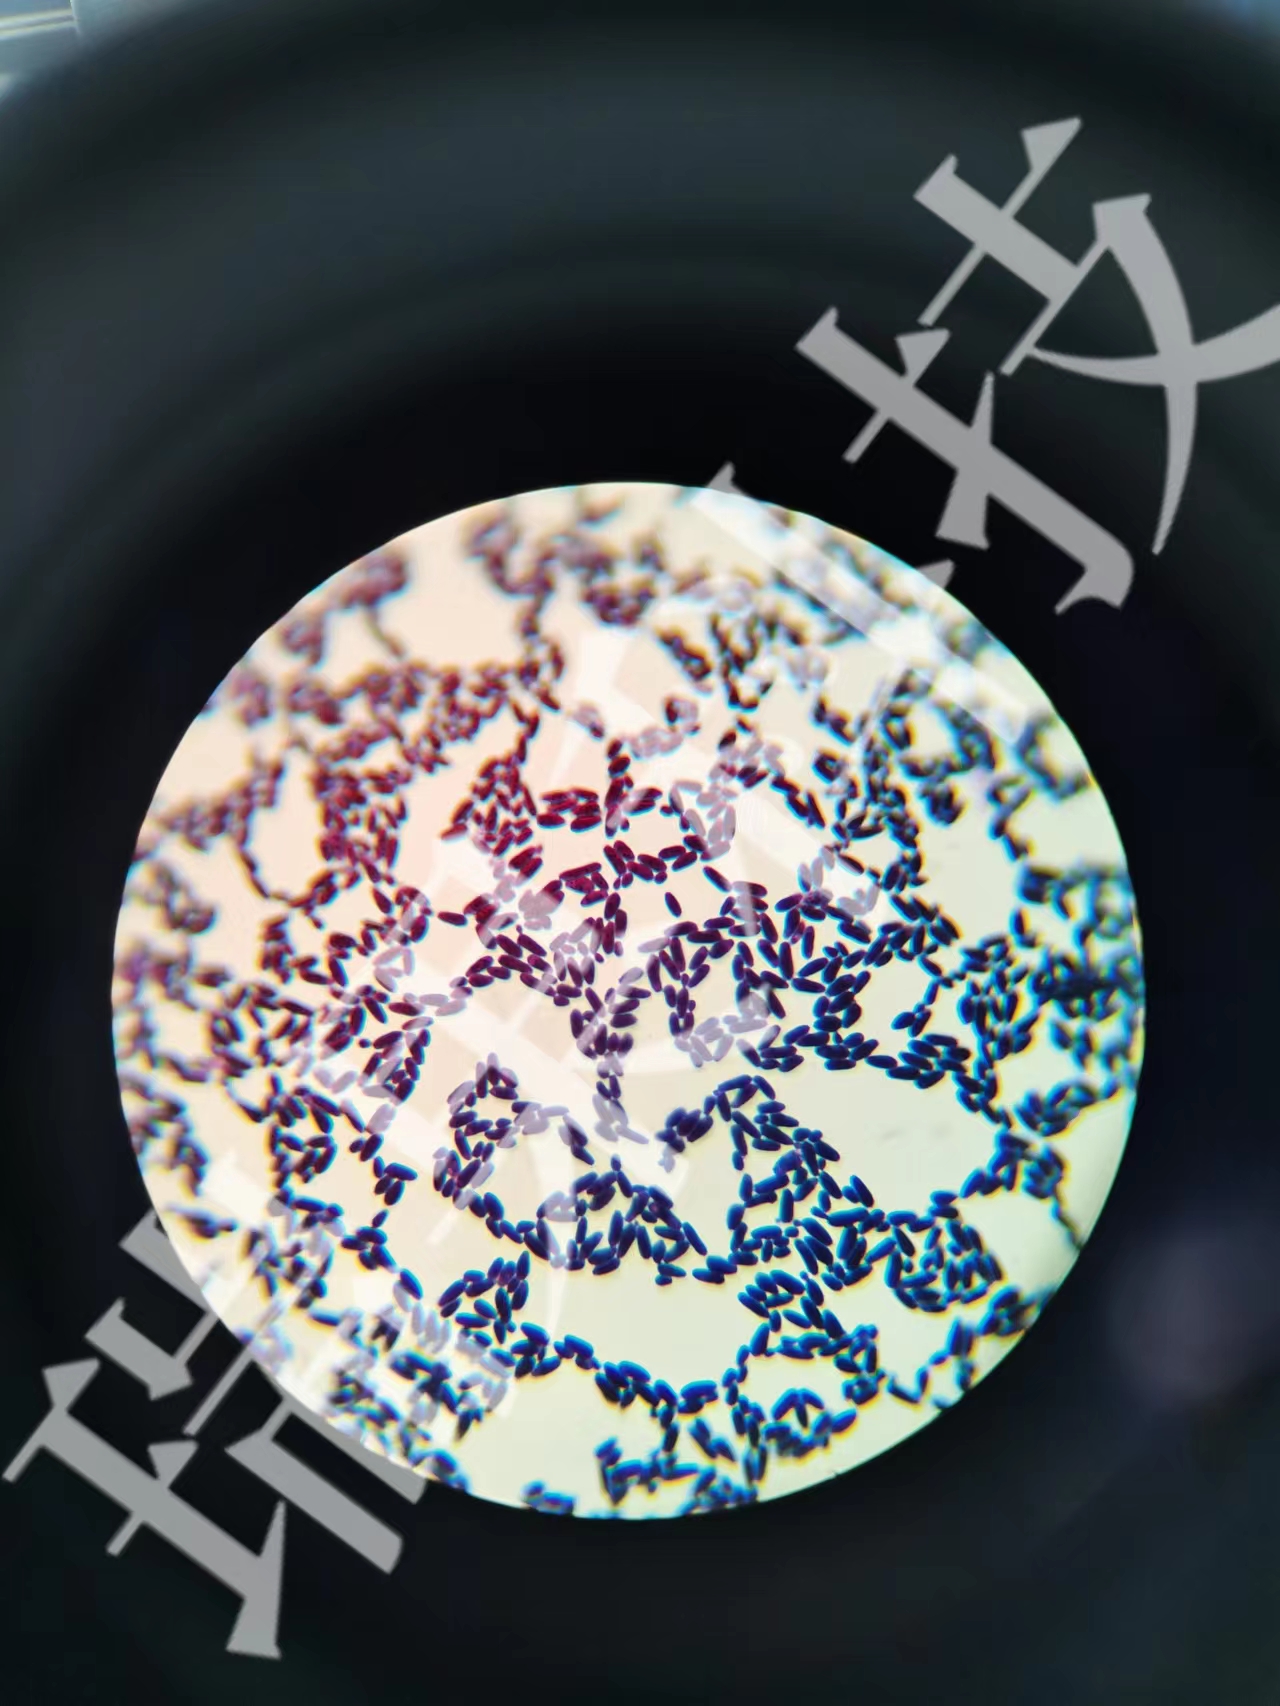

阿辛蓝染色:细胞化学染色是形态学与化学或生物化学相结合的一种检查技术。临床采用阿利新蓝染色法进一步鉴别各类血细胞提高对急性早幼粒细胞白血病诊断具有重要意义。

阿辛蓝染色:细胞化学染色是形态学与化学或生物化学相结合的一种检查技术。临床采用阿利新蓝染色法进一步鉴别各类血细胞提高对急性早幼粒细胞白血病诊断具有重要意义